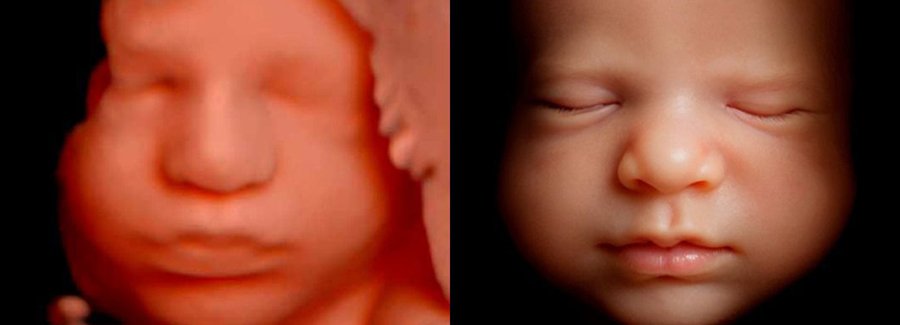

Often referred to as 5D, HD or FRV (fetal realistic view), 5D/HD is the newest development in pregnancy imaging. It captures and combines high definition volume data to create automated images with amazing color and clarity so you can see your baby as though you were looking from inside the womb.